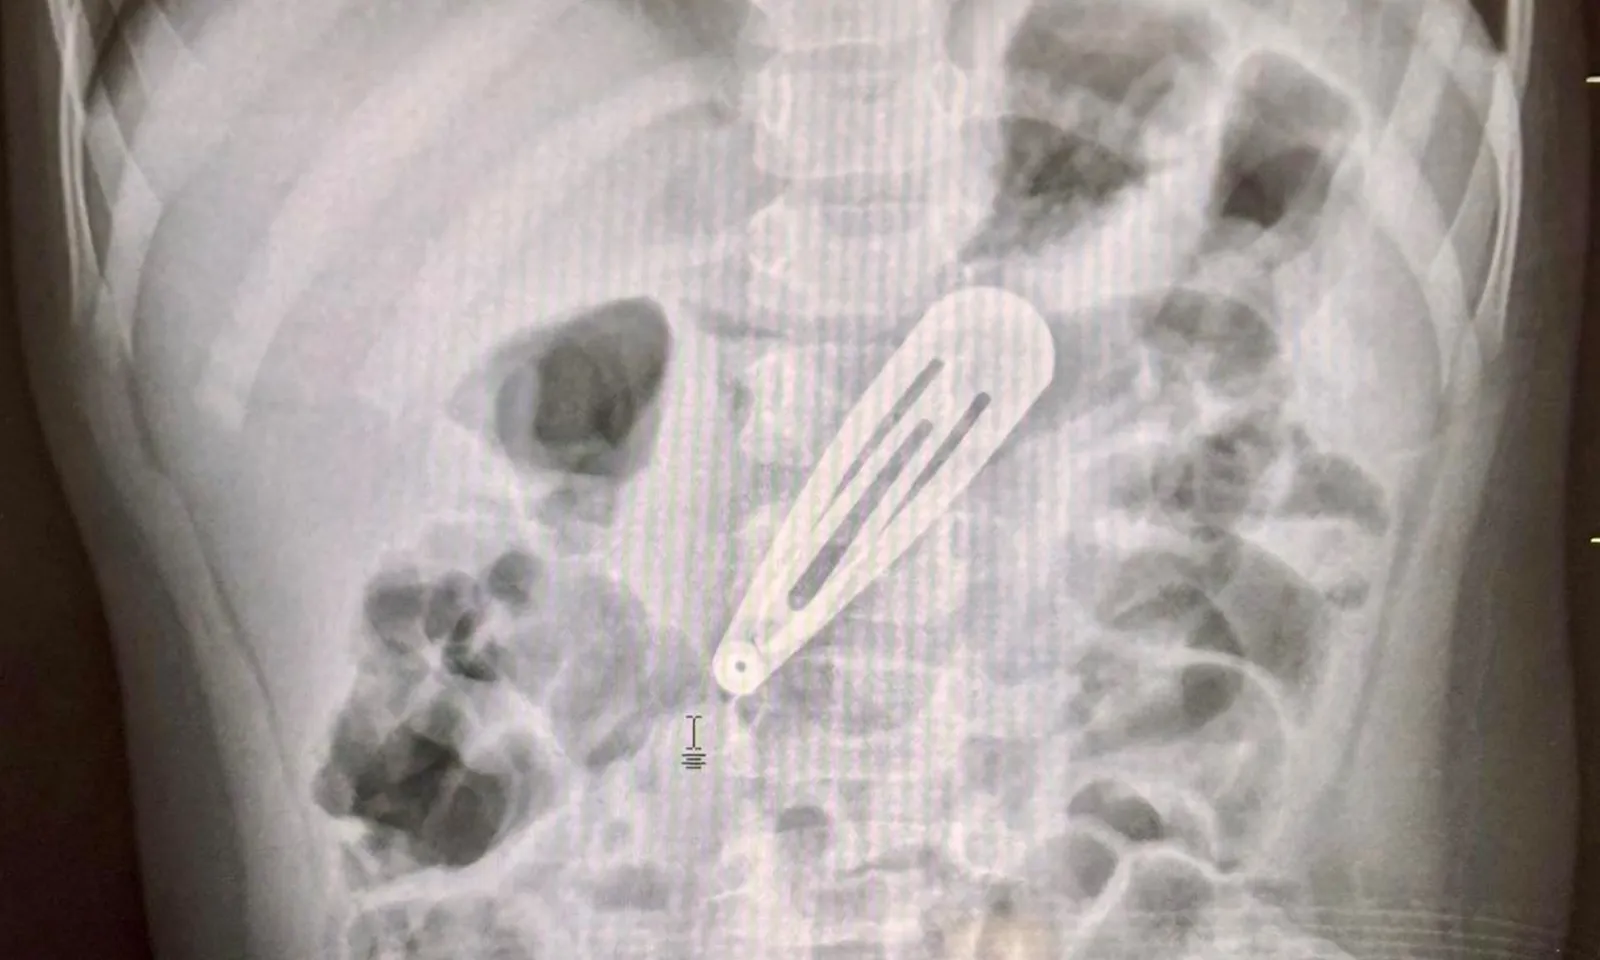

- Bé nuốt kẹp tóc kim loại, vào dạ dày, gây ho nhẹ, nôn trớ.

- X-quang xác định dị vật trong dạ dày, gần thân vị.

- Nội soi gắp dị vật thành công, không gây tổn thương niêm mạc.

- Trẻ nhỏ dễ nuốt dị vật do khám phá bằng miệng, cần cẩn trọng.

- Phụ huynh cần đưa trẻ đến viện ngay khi nghi ngờ nuốt dị vật, tránh mẹo dân gian.